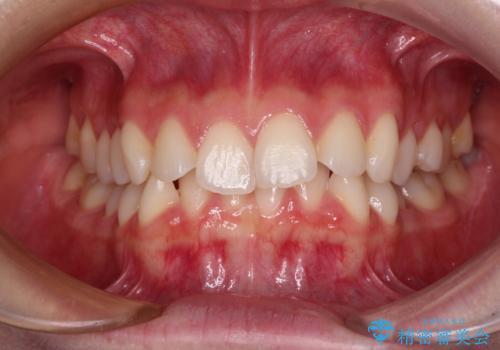

- 前歯のデコボコと下の前歯が隠れてしまう咬み合わせを気にして来院された患者様です。

インビザラインによる上下歯列の拡大と、IPR(歯と歯の間を削る)にるスペースの獲得により、口元のデコボコとディープバイトを改善することとしました。